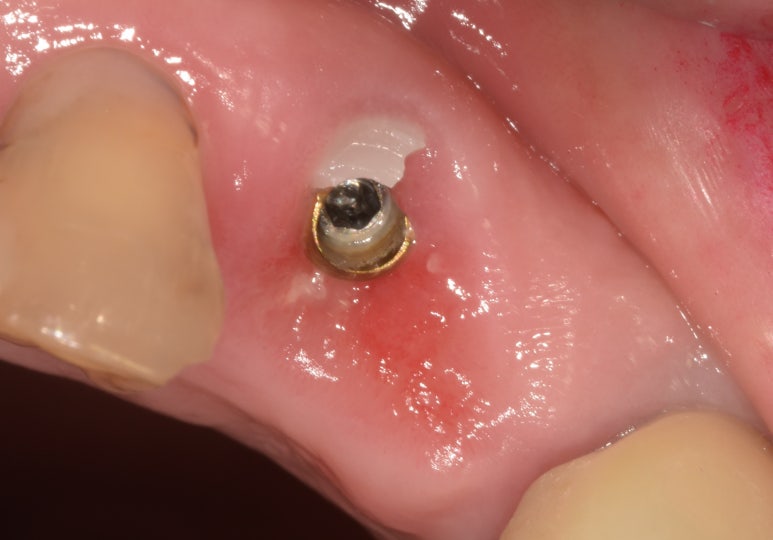

(좌) 앞니임플란트 시 지르코니아 어버트먼트를 장착한 상태

(우) 어버트먼트가 깨져 크라운과 함께 떨어진 상태

(좌) 2022-06-17 (우) 2023-02-04

지금 소개해드리는 환자분이 바로 이런 케이스였는데요.

앞니임플란트를 하셔서 금속으로 어버트먼트를 제작할 경우 색상이 비춰보일 수 있어

치아 색상과 유사한 지르코니아 어버트먼트를 하셨던 환자분입니다.

그런데 환자분께서 문에 부딪히는 바람에 이 어버트먼트가 깨져 크라운과 함께 탈락하고 말았습니다.

깨진 어버트먼트와 떨어진 크라운

일단 엑스레이를 촬영해보니 다행히도 임플란트 픽스처는 깨지지 않은 것으로 확인되었고,

픽스처가 뼈와 잘 유착되어 있는지 수치로 체크한 결과 이상이 없어서 1~2주 정도 지켜본 후

어버트먼트와 크라운만 다시 제작해 붙여드렸습니다.